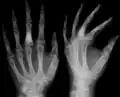

Abnormal bone growth such as shortening or thickening and deformity may be observed in patients of Ollier disease. These bone lesions are visible at birth using radiography but are usually not screened or examined for until clinical manifestations present during early childhood. However, some patients may exhibit no signs of any symptoms.[1] One study found thirteen to be the mean age of diagnosis in patients with Ollier disease. In an X-ray, there would normally be the presence of several homogeneous lesions of an oval or elongated shape with bone edges that are slightly thickened.[3] With age, these lesions may calcify and appear as diffusely minute spots or stippled. Fan-like septations or streaks would be indicative of the presence of several enchondromas. Early detection and consistent and repeated monitoring is important in order to prevent and treat any potential bone neoplasms.